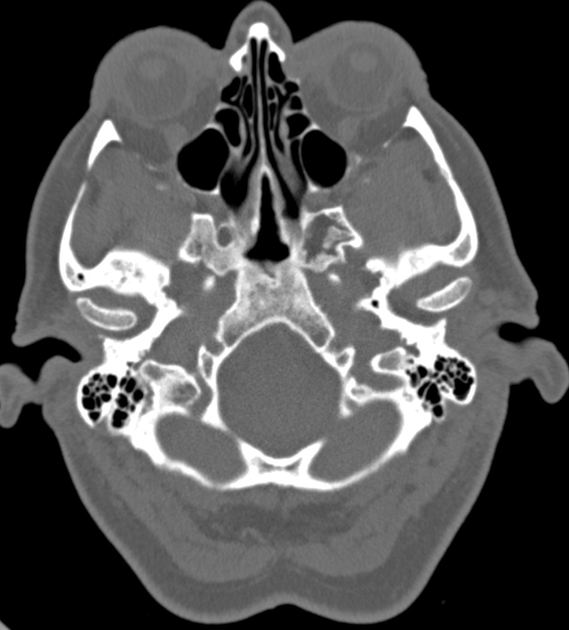

Ct skull base anatomy. You can however go directly to any section using the links below. B axial ct image with color coded overlay shows the skull base bones. The skull base can be evaluated by computed tomography ct which will demonstrate the bony structures of the skull base with its foramina and fissures for vessels and cranial nerves the temporal bone and sinonasal cavities.

Ct anatomy of skull base. Blue central skull base csb purple posterior skull base teal anterior skull base asb. Foramina of the skull base and the structures that pass through them.

Cranial foramina for further details. A axial three dimensional reconstructed ct image with color coded overlay shows the skull base sections. Ct anatomy of skull base.

Blue temporal bones fuchsia nasal bones green ethmoid bone light pink vomer purple occipital bones teal sphenoid bone yellow zygomatic bones. Basic anatomy review the bones sutures and fissures that comprise the skull base. Detailed anatomy enter this module for a more detailed review of skull base anatomy.

The base of the skull is perforated by numerous foramina which allow vessels and nerves to pass through the base of the skull allowing the intracranial cavity to communicate with the rest of the body see main article. Skull ct anatomy the sagittal suture is the line where the right and left parietal bone are in contact. A noncontrast sinus or skull base ct which covers the mastoids temporal bone and entire skull base is recommended and intravenous contrast is not usually necessary as the mri will provide soft tissue detail.

Ct is more sensitive in detecting fibro osseous skull base lesions calcification and sclerosis. The module interface is meant to mimic a radiology workstation with adjacent image scrolling via arrow keys and or mouse wheel button. Navigating the skull base identify the petro occipital fissure to navigate the major structures of the skull base.